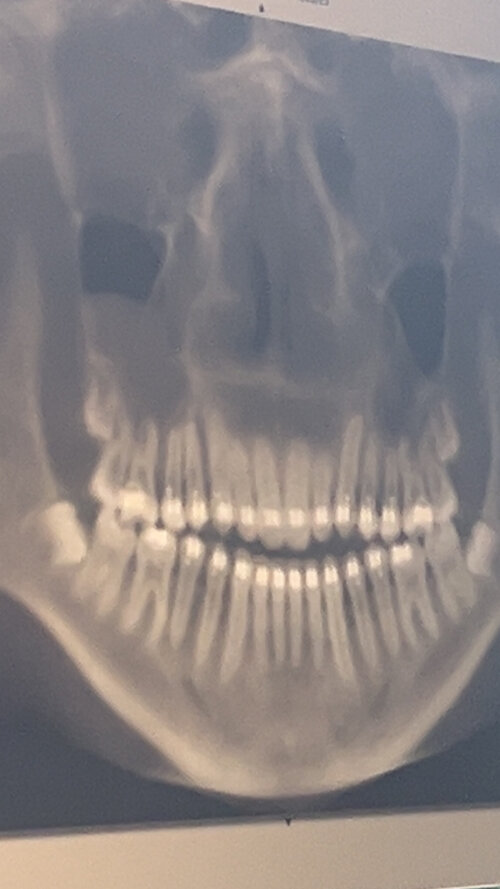

Then my aunt and the orthodontist were talking, and the orthodontist said, “I can definitely tell he Googles a lot, but when he’s older and his teeth are straight because of me, he can get jaw surgery,” and went on to describe it “as cutting the jaw in half and repositioning it” making it sound really bad. Here are Xrays and pictures of my progress so far. Left is the Start, The right is 6 weeks ago